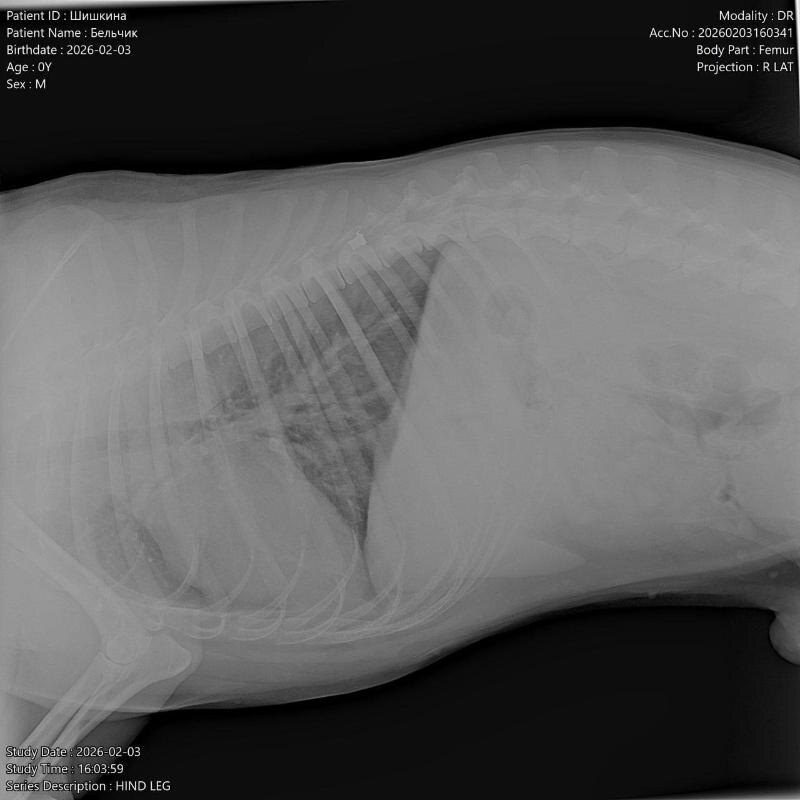

Пса привезли в ветклинику, где рентген показал пулю, которая застряла в позвоночнике и перелом таза. Волонтеры предполагают, что собаку сначала подстрелили, а затем сбили машиной. Они обратились к правоохранительным органам с просьбой расследовать этот случай.

Фото: «Феникс»